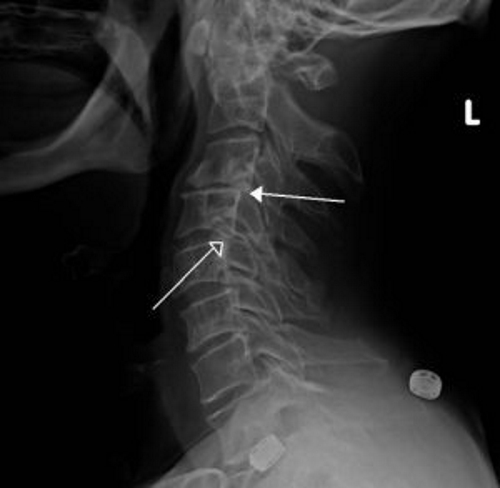

- Рентгенография в нескольких проекциях позволяет выявить смещение позвонков, определить его степень и оценить выраженность патологических изменений в хрящевых тканях.